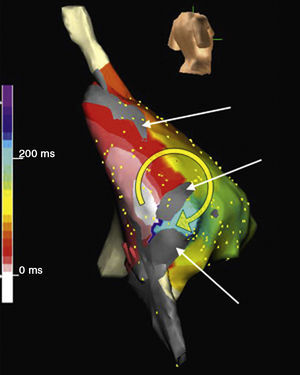

Figura 11. Cartografía electroanatómic (Navx®) de taquicardia auricular macrorreentrante en paciente intervenido por atresia tricuspídea en visión posterolateral derecha. Nótese las zonas inexcitables de bajo voltaje (gris). La escala de tiempos marca arbitrariamente el punto de inicio (blanco) por detrás de un istmo entre dos zonas inexcitables. La activación gira en torno a una de las zonas inexcitables (blanco a rojo→amarillo→verde→azul) para volver a pasar el istmo. La aplicación de radiofrecuencia en este punto interrumpió la taquicardia.

En su forma más sencilla, la TAMR de cicatriz es un circuito localizado en la pared lateral de la AD, en cuyo centro hay una línea de bloqueo, constituida por la misma cicatriz (Figura 6, Figura 7, Figura 11). El punto de giro inferior localizado entre el extremo de la cicatriz y la vena cava inferior es estrecho y suele ser una zona de conducción lenta. El punto de giro superior puede ser el extremo de la cicatriz o el orificio de la cava superior, que se puede integrar funcionalmente en el obstáculo central (Figura 6, Figura 7). En aurículas muy dilatadas, especialmente tras la cirugía de Fontan, se puede encontrar zonas inexcitables, de bajo voltaje, en las paredes de AD (Figura 11) que contribuyen a canalizar los circuitos de TAMR21, 22, 23. En pacientes sometidos a cirugía de Mustard o Senning, a la complejidad de las barreras cicatriciales se añade la enorme dificultad de acceso a las porciones de las aurículas aisladas por los parches utilizados para reconducir el flujo sanguíneo24, 25.